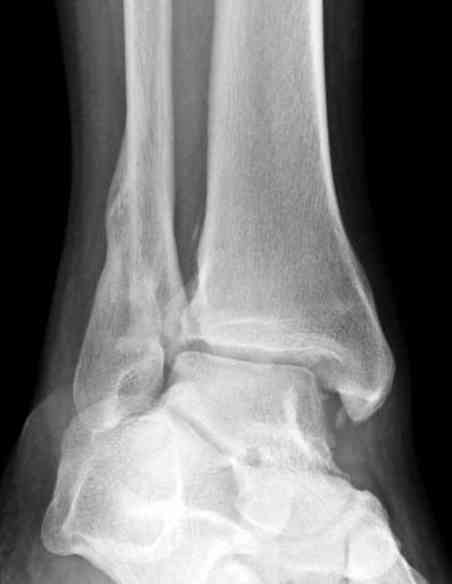

Здесь представлено решение похожей проблемы. Больной в течение года лечился консервативными мерами, и боли в голеностопе были основным показанием к операции.

Проведена обычная стандартная процедура по исправлению неудовлетворительного состояния голеностопного сустава, где кроме удлинения малоберцовой с применением compression tension device за проксимальный конец пластины, проведено замещение трикортикальным графтом из крыла, освобождение синдесмоза и медиальной щели от

фибротических масс с фиксацией.